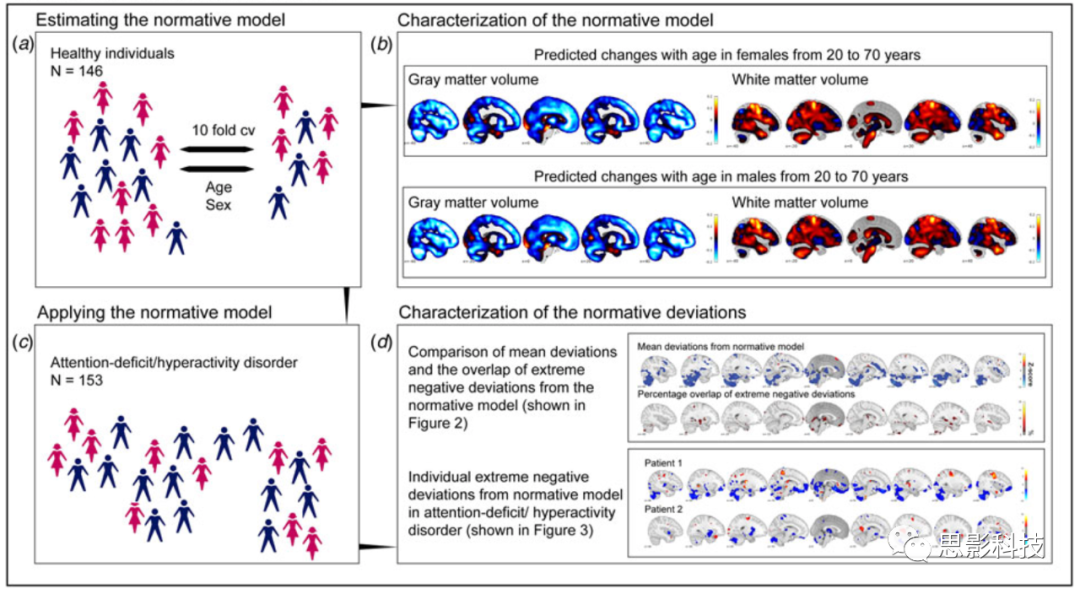

6、Psychological Medicine:个体差异与平均患者:使用标准模型表现ADHD的异质性

与一般的病例对照分析不同,一般的病例对照分析假设患者和对照组之间有明显的区别,因此引入了“普通患者”的概念,Thomas Wolfers等人则提出了一种全新的方法来模拟具有相同生物异质性精神障碍的人的个体差异,分别描述每个患者的生物学特性,从而深入了解持续性注意力缺陷多动障碍(ADHD)的不同特征。该研究采用一种标准的建模方法,绘制了参照整个生命周期中标准大脑结构变化的个体间差异,以检查病例对照分析掩盖个体间差异的程度。

在个体层面上,持续性ADHD经常偏离标准模型。并且多动症被试之间超过2%的重叠只在少数大脑位点被观察到。与健康的人相比,多动症参与者的小脑和海马体的灰质显著减少。通常的病例对照比较,掩盖了持续注意力缺陷多动症个体间的脑生物学差异。该研究的结果表明,“一般ADHD患者”的信息价值有限,这为在个体水平上探索ADHD生理差异的必要性和实现这一目标的实际手段提供了首证据。

原文:Individual differences v. the average patient: mapping the heterogeneity in ADHD using normative models

DOI:https://doi.org/10.1017/S0033291719000084